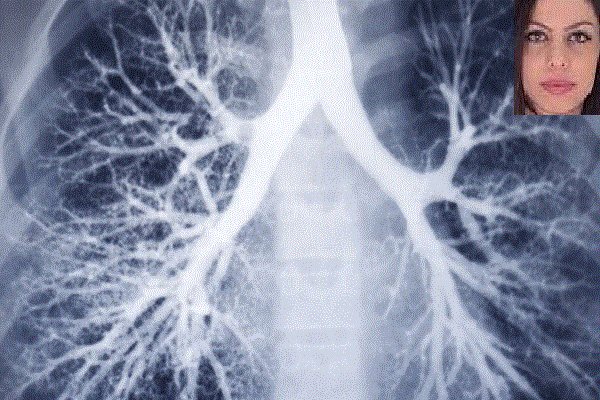

محققان امریکایی با همکاری دکتر «صبا امرانی» موفق به ساخت دستگاه پوشیدنی شده اند که از قابلیت تحلیل صدای خس خس دستگاه تنفسی برخوردار است. صدای خس خسی که از دستگاه تنفسی بسیاری از افراد شنیده می شود به معنای مشکل داشتن دستگاه تنفسی است. محققان امریکایی موفق به ساخت گجت پوشیدنی شده اند […]

محققان امریکایی با همکاری دکتر «صبا امرانی» موفق به ساخت دستگاه پوشیدنی شده اند که از قابلیت تحلیل صدای خس خس دستگاه تنفسی برخوردار است.

صدای خس خسی که از دستگاه تنفسی بسیاری از افراد شنیده می شود به معنای مشکل داشتن دستگاه تنفسی است. محققان امریکایی موفق به ساخت گجت پوشیدنی شده اند که صدای خس خس کاربرانش را تحلیل کرده و به پزشکان اجازه می دهد تا نوع تنفس بیمار را تشخیص و آنها را از میزان خطری که با آن مواجه هستند، آگاه کند.

این گجت با همکاری محقق ایرانی دانشگاه کارولینای شمالی «صبا امرانی» Saba Emrani و «حمید کریم» Hamid Krim از محققان مرکز بنیاد علوم ملی در زمینه مهندسی نانوسیستم ها((ASSIST ساخته شده است. صبا امرانی از فارغ التحصیلان دانشگاه صنعتی امیرکبیر است.

این گجت ترکیبی از نرم افزارها و حسگرهایی است که با ارزیابی صدای خس خسی که از دستگاه تنفسی شخص شنیده می شود به کنترل سلامت کاربرانش می پردازد. این دستگاه از دو بخش اصلی تشکیل شده است. بخش اول شامل حسگرهایی است که به بیمار وصل شده و در تمامی فعالیت های روزمره به بدن شخص متصل هستند. حسگرهای این بخش با حرارت بدن کاربران فعال می شوند. اما بخش دوم شامل نرم افزارهایی است که بر فعالیت حسگرها نظارت می کنند.

زمانی که نرم افزار از طریق حسگرها، صدای خس خس را تشخیص دهد از الگوریتم و روش خاصی برای ارزیابی زمان شروع و همینطور شیوه صداها استفاده می کند. گجت با تحلیل این عوامل می تواند نقطه ای از ریه که مشکل دارد را شناسایی کرده و اطلاعات مهمی را در اختیار پزشکان قرار دهد تا بتوانند تصمیمات بهتری را درباره شیوه درمان بیمار اتخاذ کنند.

محققان امیدوارند موفق به طراحی نرم افزاری شوند که بتوان آن را به عنوان برنامه در اسمارت فون ها نصب و حسگرها به صورت وایرلس با بدن کاربران ارتباط برقرار کرده و بتوان به سنجش میزان سلامت کاربران پرداخت.